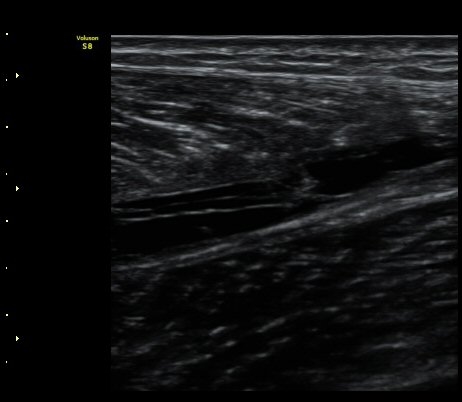

ºñº¹±Ù Ⱦ´Ü¸é°Ë»ç¿¡¼­ ºñº¹±Ù ³»Ãø, °¡Àڹٰ̱ú Á¢ÇÕ ºÎÀ§ÀÇ ÆÄ¿­°ú ¼ö¾× Àú·ù°¡ °üÂûµÊ(±×¸² 4)